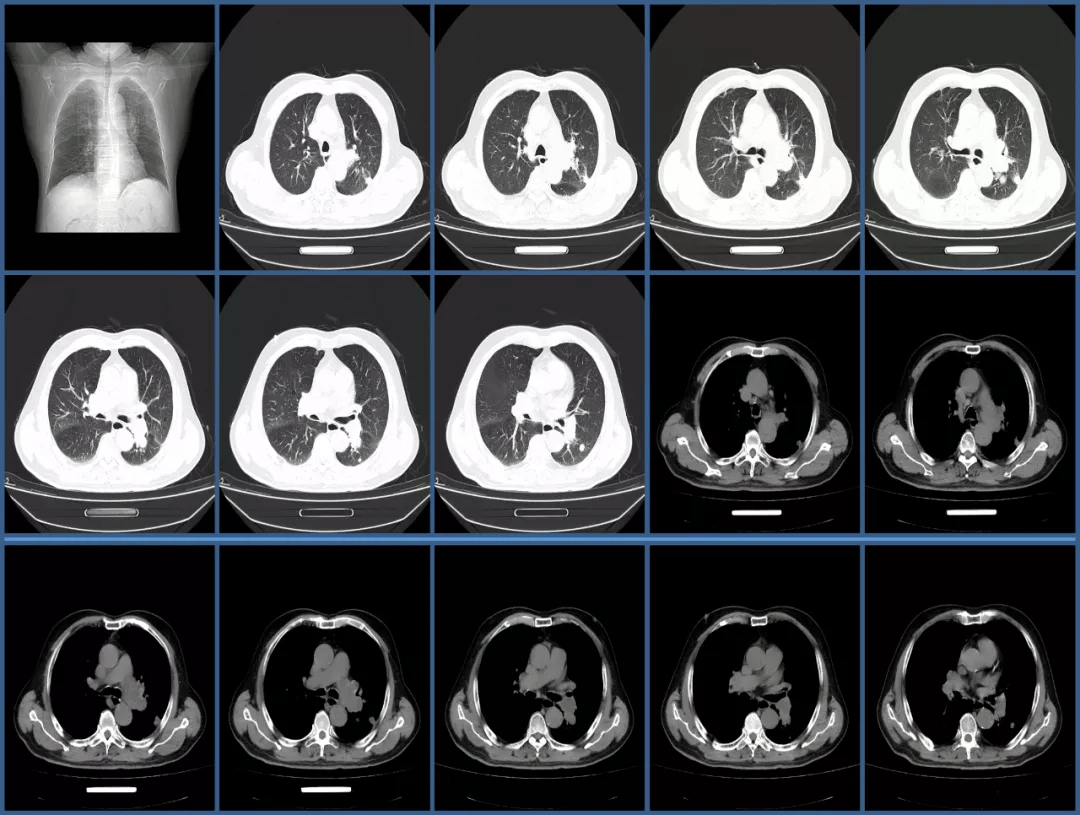

肺动脉内的充盈缺损还有可能是这个病,你知道吗?

低热肺部阴影充盈缺损血栓以外还有哪些其它原因值得探寻